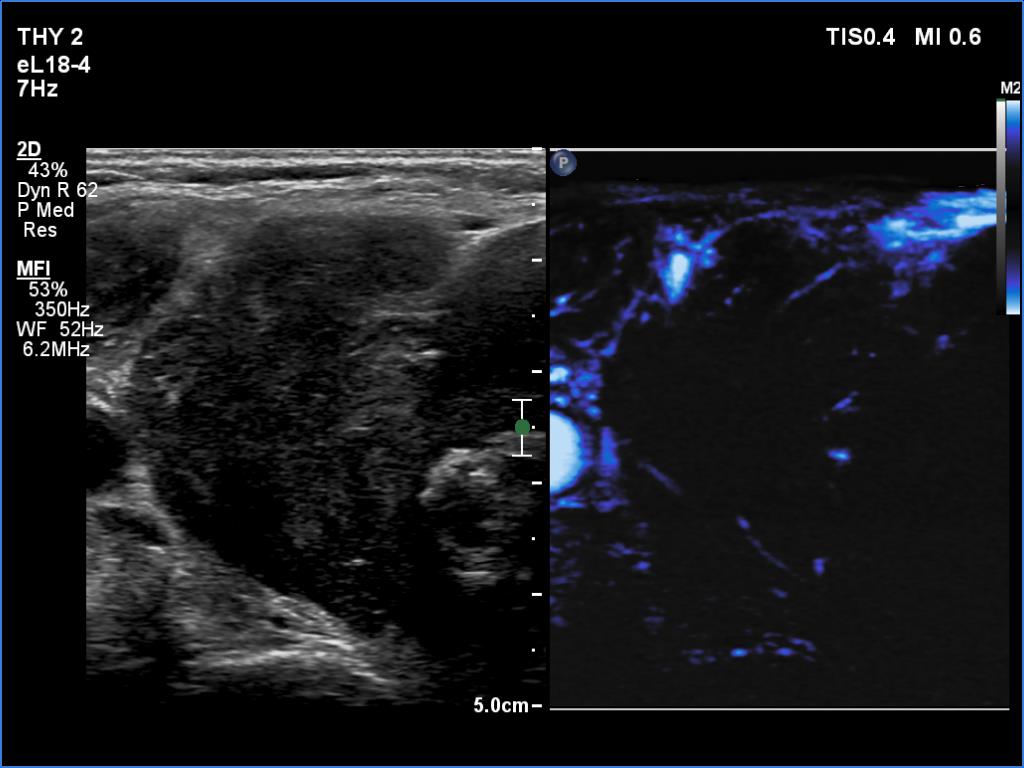

Thyroid cancers - case 1174 (ultrasonographic picture 9)

Right lobe, transverse view, microflow imaging. There are small number of vessels.